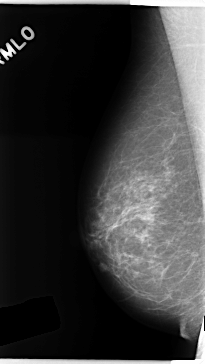

ics_version 1.0 filename C-0241-1 DATE_OF_STUDY 22 2 1995 PATIENT_AGE 63 FILM FILM_TYPE REGULAR DENSITY 2 DATE_DIGITIZED 28 4 1998 DIGITIZER LUMISYS LASER SEQUENCE LEFT_CC LINES 4752 PIXELS_PER_LINE 2624 BITS_PER_PIXEL 12 RESOLUTION 50 OVERLAY LEFT_MLO LINES 4744 PIXELS_PER_LINE 2512 BITS_PER_PIXEL 12 RESOLUTION 50 OVERLAY RIGHT_CC LINES 4712 PIXELS_PER_LINE 2656 BITS_PER_PIXEL 12 RESOLUTION 50 NON_OVERLAY RIGHT_MLO LINES 4728 PIXELS_PER_LINE 2656 BITS_PER_PIXEL 12 RESOLUTION 50 NON_OVERLAY |